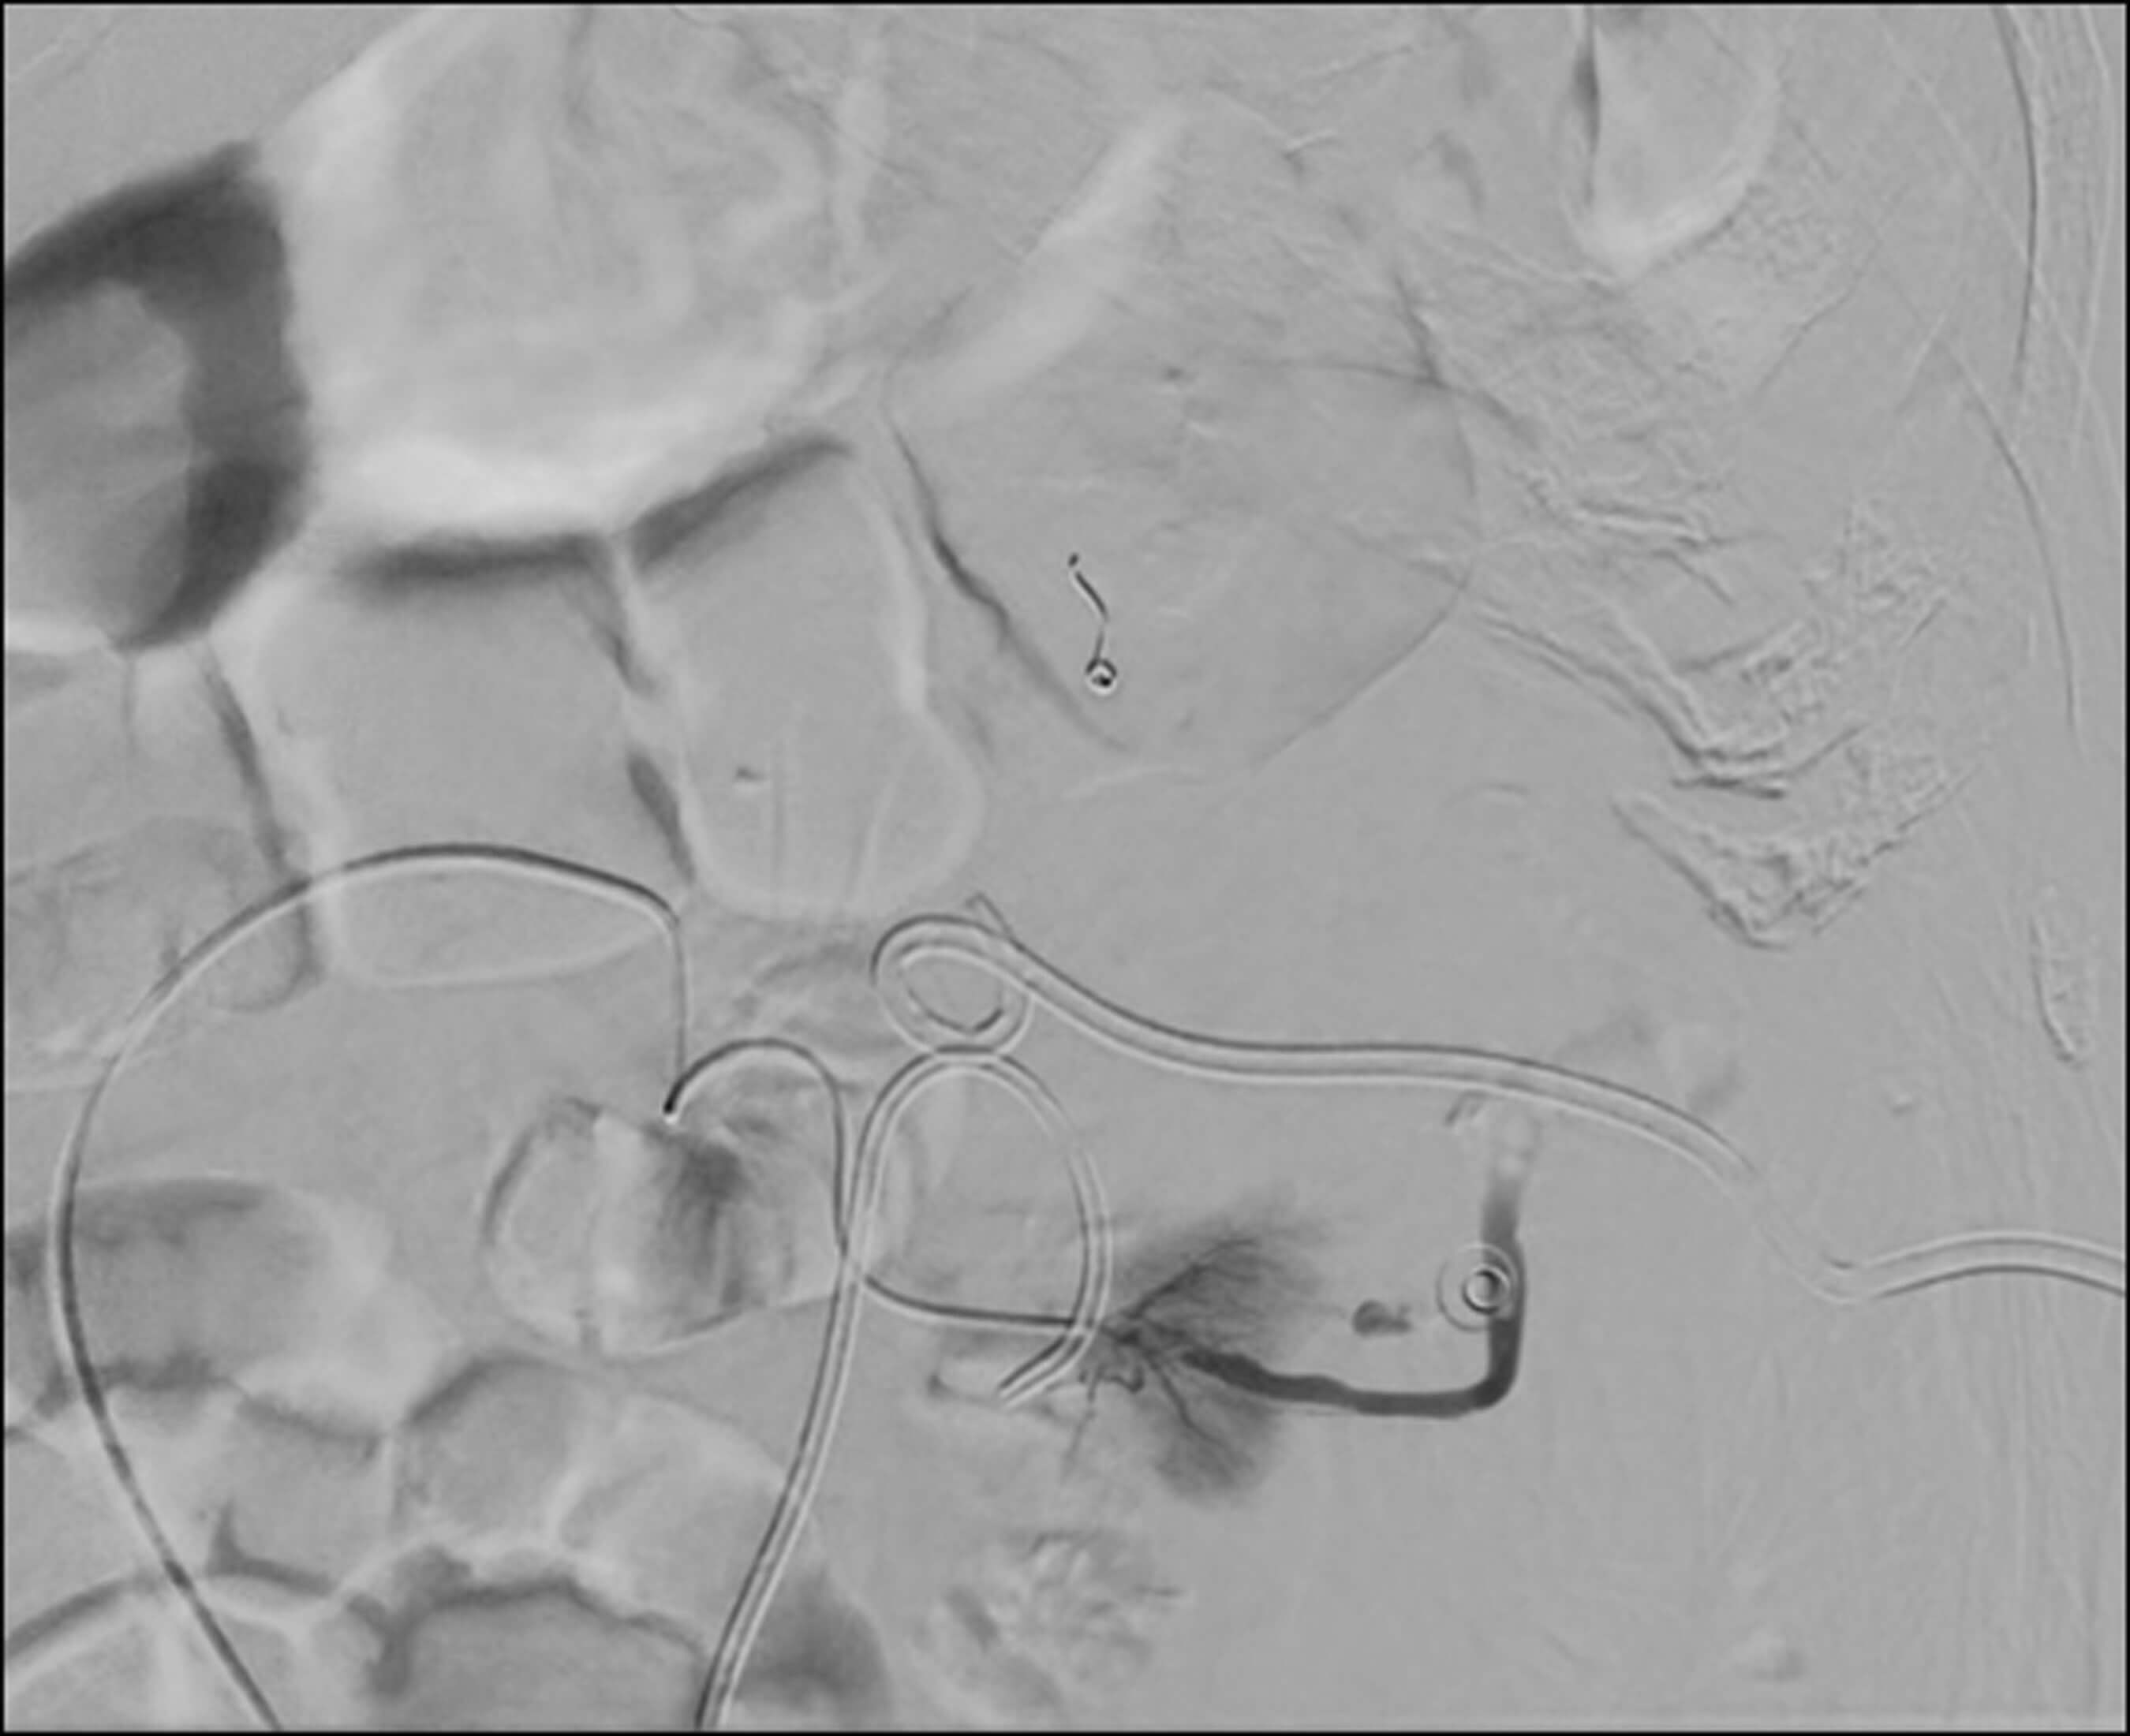

A 68-year-old male patient with a history of nephroureterectomy for transitional cell carcinoma presented with recurrent disease, causing obstruction in the remaining left single kidney. The patient has a ureteric stent and nephrostomy in situ (Figure 3). During a routine nephrostomy change, he was found to have a renal haematoma with persistent acute bleeding. Interventional radiology arranged embolisation of the inferior segmental artery of the left kidney as shown in Figure 3.

Figure 3.